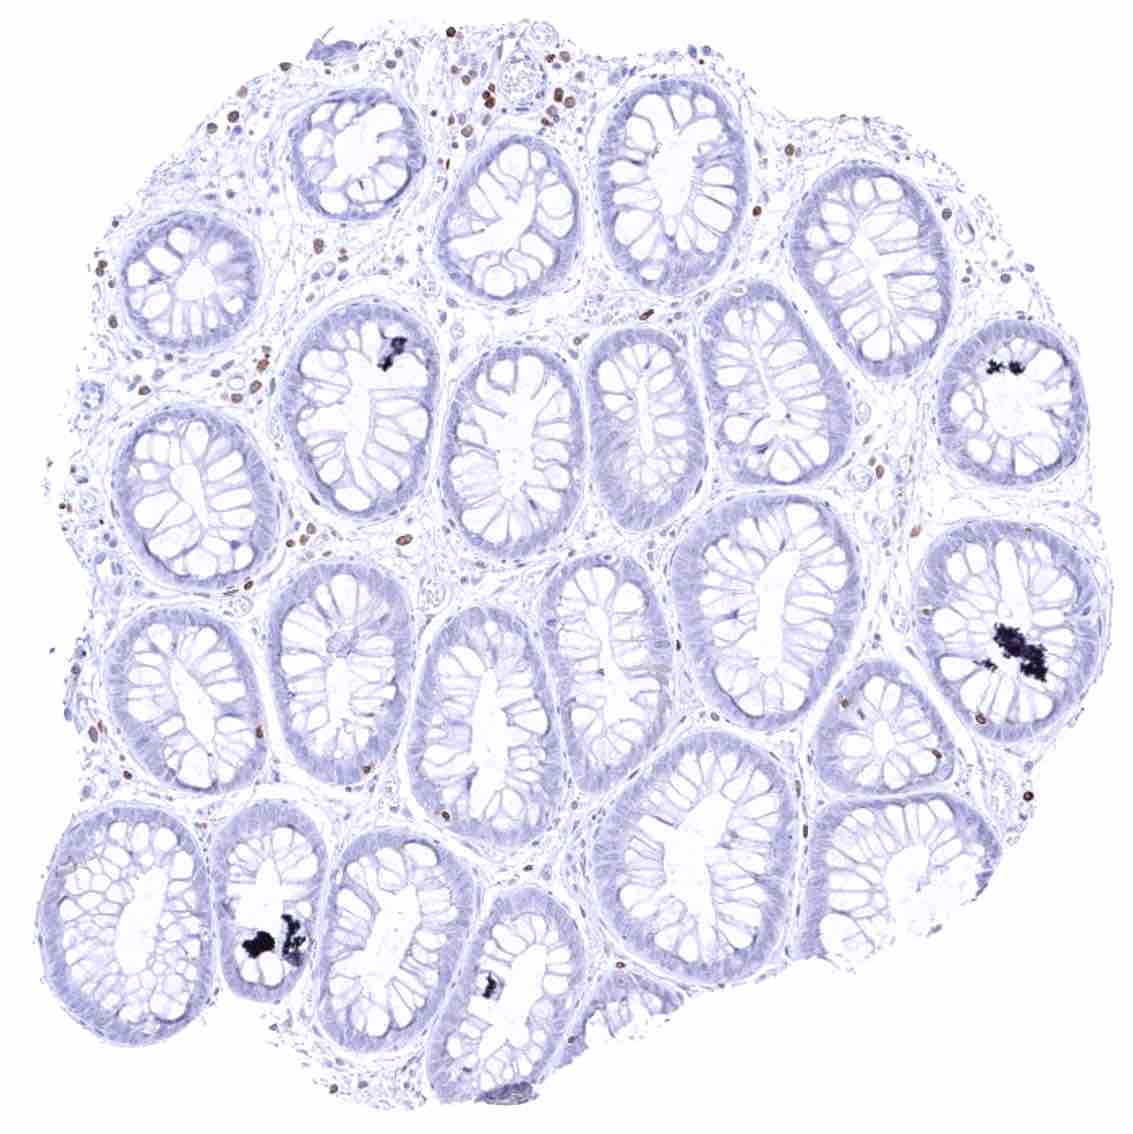

Duodenum, mucosa – Cytoplasmic bcl-2 staining is largely limited to lymphocytes. The epithelium is mostly negative, but a weak staining occurs in some crypt cells.